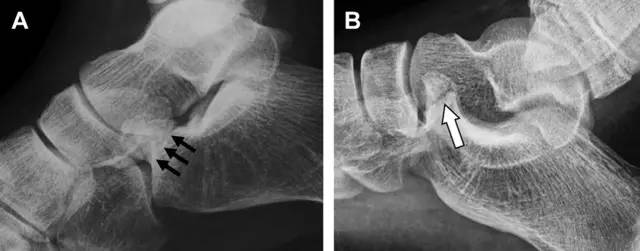

20 跟骨前突骨折

呈 Y 形的分歧韧带附着于跟骨前突上,是维持踝关节跖屈和背屈稳定性的重要结构。跟骨前突骨折常发生于足跖屈内旋、分歧韧带被牵拉时,或者足背屈外旋、骰骨和距骨挤压前突时。而这些骨折在初次 X 线检查时常常被漏诊掉。踝部侧位片诊断这些骨折最佳,准确诊断的关键点在于,必须仔细查看是否存在骨皮质中断(图 6)。如果侧位片可疑,建议加做斜位片协助诊断。

图 6 跟骨前突骨折。A 侧位片示跟骨前突骨折(箭头),与舟骨的重叠使骨折显示模糊;B 另一位患者的侧位片示内翻损伤所致的骨折(箭头),这种损伤机制引起小块的骨折